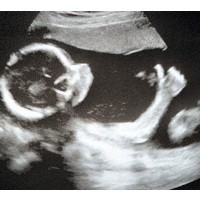

Posisi bayi yang mengacungi jempol ini sungguh tidak biasa. Sang ibu, Marie Boswell, 35 tahun mengatakan keluarga dan teman-temannya dibuat terkagum-kagum dengan jempol tanda 'oke' si bayi berusia 20 minggu dari dalam rahim yang terbaca jelas dari hasil scan USG.

"Ini benar-benar lucu, jarinya begitu terlihat jelas, kami tidak percaya itu, dia tampak seperti memakai sarung tinju," kata Marie yang melakukan scan USG di Wythenshawe Hospital seperti dilansir dari Telegraph, Minggu (23/5/2010).

Marie sebelumnya telah memiliki anak perempuan bernama Olivia, berusia 10 tahun. Marie melakukan scan untuk memeriksa tulang belakang bayi karena posisinya tidak biasa.

Tapi pihak rumah sakit sudah memberikan dengan jelas kondisi si jabang bayi yang diharapkan akan lahir pada bulan September 2010. Kedua orangtua si jabang bayi juga percaya acungan jempol itu tanda ingin memberitahukan si bayi baik-baik saja.

Gerry Jackson, ahli sonogram di Wythenshawe mengatakan, "Ini sangat tidak biasa melihat jempol bayi yang begitu jelas. Ini hal yang indah dan kita bisa mendapatkan gambar yang begitu jelas".